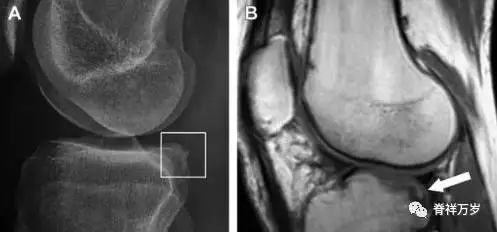

10胫骨后外侧碎片骨折

胫骨后外侧小片骨皮质的压缩性骨折,可能是旋转移位损伤的唯一证据(图 3)。这种骨折在常规膝关节平片很难发现,若怀疑存在骨折,行下肢内旋斜位片检查可诊断。

图 3 胫骨后外侧碎片骨折

A 正位片示胫骨后外侧处可见一压缩骨折的小碎片(方框)。这是胫骨撞击股骨外侧髁旋转移位时所致。B 另一位患者的 MRI 矢状位 T1 加权像示胫骨后外侧骨折碎片(箭头)。